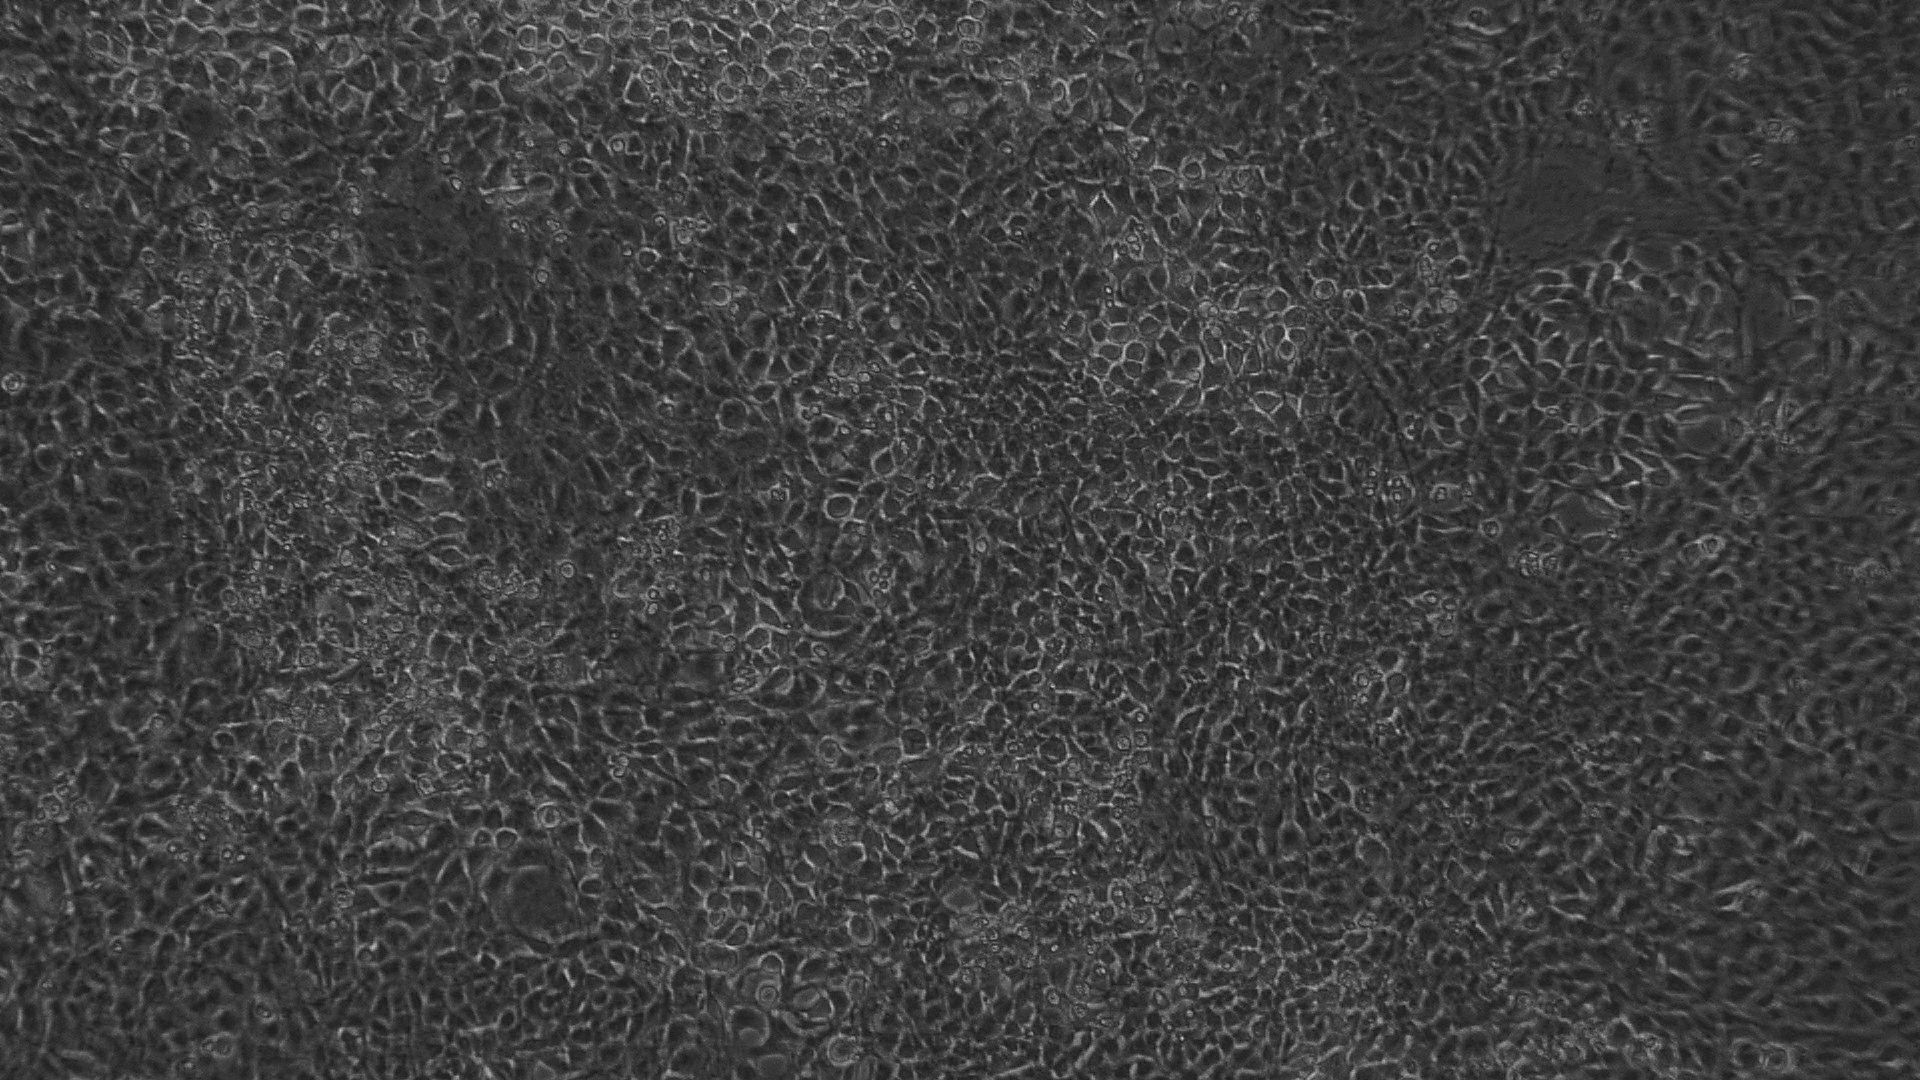

The entire plate was observed at an interval of every 24 h; up to 72 h in an inverted phase-contrast tissue culture microscope (Labomed TCM-400 with MICAPSTM HD camera) and microscopic observations were recorded as images. Any detectable change in the morphology of the cells, such as rounding or shrinking of cells, granulation, and vacuolization in the cytoplasm of the cells, were considered as indicators of cytotoxicity.

Fig. 8: Morphological changes showing inhibition of MCF 7 cell lines by different concentrations of standard drug Doxorubicin. a: -ve control (95% ethanol), b: 0.097 µg/ml, c: 0.19µg/ml, d: 0.39 µg/ml, e: 0.78 µg/ml f: 1.56 µg/ml

In vitro anticancer actiivity of ethanolic extract of leaves of Pothos scandens Linn. was evaluated against HeLa and MCF 7 cell lines. The viability of cells was evaluated by direct observation of cells by an Inverted phase contrast microscope and MTT assay method. The morphological changes in HeLa and MCF 7 cells after treatment with the extract and standard doxorubicin are shown in fig. 5, 6, 7 and 8. The IC50 values are shown in table 4.